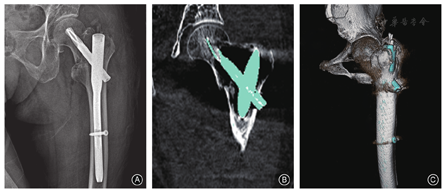

关于股骨转子间骨折术后复位质量评估,可在术后2周时行X线片及CT检查,而后进行数字化分析及精细评估。数字化技术在术后的影像学随访中,可通过不同的内植入物提取模式结合三维容积重建技术、自由截面选择的MPR技术等精确观察股骨转子间骨折术后的骨折块复位质量、内固定置放情况,从而科学指导患者术后的肢体功能锻炼进程(图7)。